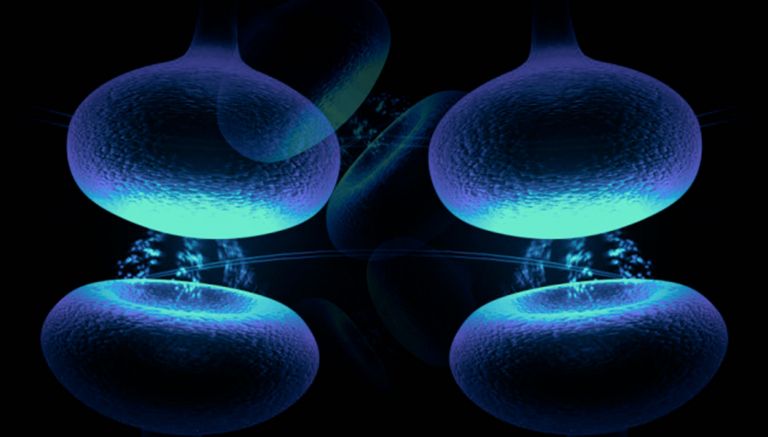

Der Hippocampus ist der größte Teil des Archicortex und ein Areal im Temporallappen. Er ist zudem ein wichtiger Teil des limbischen Systems. Funktional ist er an Gedächtnisprozessen, aber auch an räumlicher Orientierung beteiligt. Er umfasst das Subiculum, den Gyrus dentatus und das Ammonshorn mit seinen vier Feldern CA1-CA4.

Offenbar hatte Karl Lashley bei seinen Studien am falschen Ort gesucht. In seinen Rattenexperimenten hatte er stets Teile der Hirnrinde, also der äußersten Schicht des Gehirns entfernt. Dieses Hirnareal ist in der Entwicklungsgeschichte des Gehirns das jüngste, alle anderen hielt Lashley für zu primitiv. H.M. fehlte es aber nicht an Hirnrinde, Scoville hatte einen Teil des Mandelkerns, der Amygdala, entfernt und fast den gesamten Hippocampus. Diese Region an der Innenseite der Schläfenlappen war offenbar entscheidend für das Formen neuer Erinnerungen.

Das zeigte sich auch in Tierversuchen. „Nach den Erfahrungen mit H.M. sind tausende Untersuchungen an Ratten und anderen Tieren gemacht worden“, sagt Markowitsch. Sie alle zeigten dasselbe: Wird der Hippocampus beschädigt, beeinträchtigt das die Fähigkeit, neue Erinnerungen abzuspeichern. Buschhäher finden das Essen, das sie versteckt haben, nicht wieder und Ratten finden sich in Labyrinthen nicht mehr zurecht.

Eine weitere Merkwürdigkeit im Fall H.M: Ihm fehlte zwar das Langzeitgedächtnis, aber für ein paar Sekunden konnte er sich alles merken. Viele Versuche haben gezeigt, dass sein Kurzzeitgedächtnis in etwa so gut funktionierte wie das eines gesunden Menschen. Telefonnummern oder Wortlisten etwa konnte H.M. sich kurze Zeit merken, wurde er aber nach ein paar Minuten oder Stunden noch einmal gefragt, hatte er sie vergessen. „H.M. war der Paradefall, der gezeigt hat, dass der Hippocampus zentral ist für die Übertragung vom Kurzzeit– ins Langzeitgedächtnis“, sagt Markowitsch. Was auf lange Zeit abrufbar bleiben soll, das muss offenbar durch das Nadelöhr des Hippocampus. So haben Forscher mit bildgebenden Verfahren gezeigt, dass sich Menschen aus einer Liste von Wörtern an die am besten erinnern, bei deren Lernen der Hippocampus am stärksten aktiv war.

Der Hippocampus ist der größte Teil des Archicortex und ein Areal im Temporallappen. Er ist zudem ein wichtiger Teil des limbischen Systems. Funktional ist er an Gedächtnisprozessen, aber auch an räumlicher Orientierung beteiligt. Er umfasst das Subiculum, den Gyrus dentatus und das Ammonshorn mit seinen vier Feldern CA1-CA4.

Der Hippocampus ist der größte Teil des Archicortex und ein Areal im Temporallappen. Er ist zudem ein wichtiger Teil des limbischen Systems. Funktional ist er an Gedächtnisprozessen, aber auch an räumlicher Orientierung beteiligt. Er umfasst das Subiculum, den Gyrus dentatus und das Ammonshorn mit seinen vier Feldern CA1-CA4.